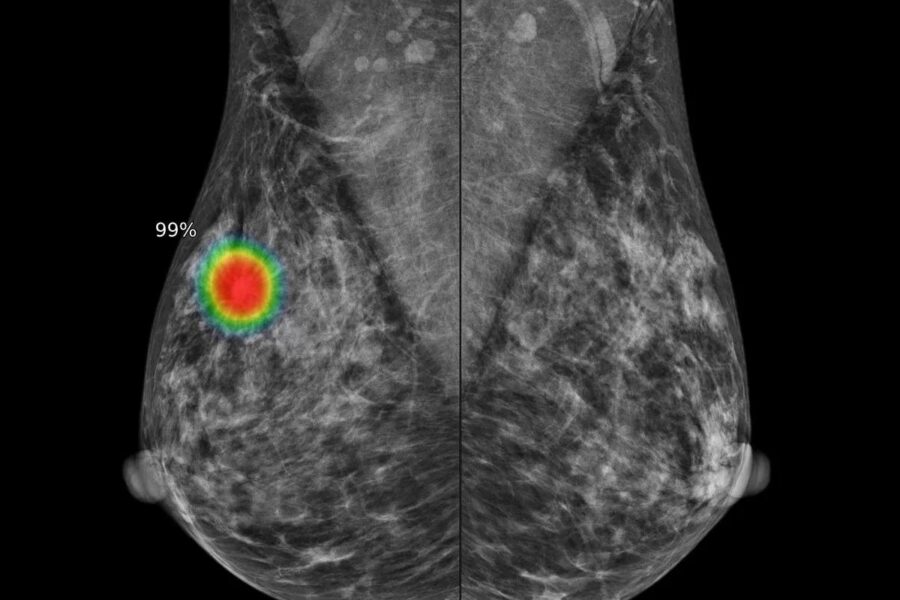

IA de Google supera ojo humano y detecta 25% más cánceres ocultos

Un sistema de IA en Reino Unido detectó 25% más cánceres de mama que métodos tradicionales. Esto puede cambiar la medicina pública para siempre.